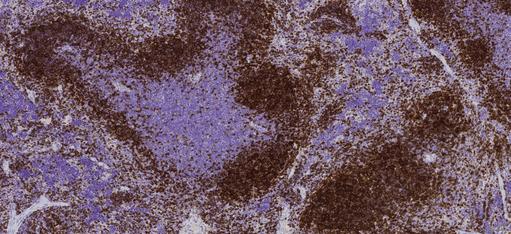

Quality Histopathology Service to Enable Your Research Advanced Molecular Pathology Laboratory (AMPL) from Institute of Molecular & Cell Biology (IMCB) is a GLP-certified histopathology laboratory that provides an integrated array of services to biomedical and pharmaceutical industries. It brings together expertise across multiple disciplines to provide a one-stop histology services. New technologies at AMPL enable research groups to deliver innovative and cutting-edge contribution to basic as well as translational research, therapeutic target validation and drug safety evaluation. AMPL handles rodent and non-rodent tissues, we offer well-established SOPs and advanced equipment to provide histo services. • Rodent necropsy • Laser capture microdissection (LCM)* • Routine and specialised histology processing* • Tissue microarrays (TMA)* • Cryo tissue processing and cryotomy* • Veterinary pathology evaluation* • Special Staining* • Veterinary diagnostic services • Immunohistochemistry and immunofluorescence* • Quality assurance at each step of service • Antibody evaluation and optimisation • GLP in vitro toxicity testing facility (in progress) • Quality scanning and digital imaging* • Image analysis*